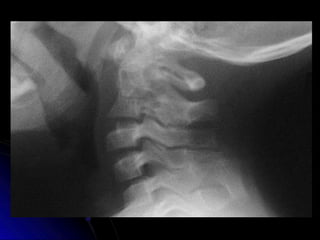

Cervical Lateral

Estructuras Visualizadas

•Cuerpos Vertebrales C2-T1

•Espacios Discales

•IAO (ADI)

•PE’s, Lámina, Pedículos,

•Pilares Articulares y Facetas

•Sombra Aire Traqueal

•Línea de George & línea Espino-laminar

•Silla Turca

•Arcos C1